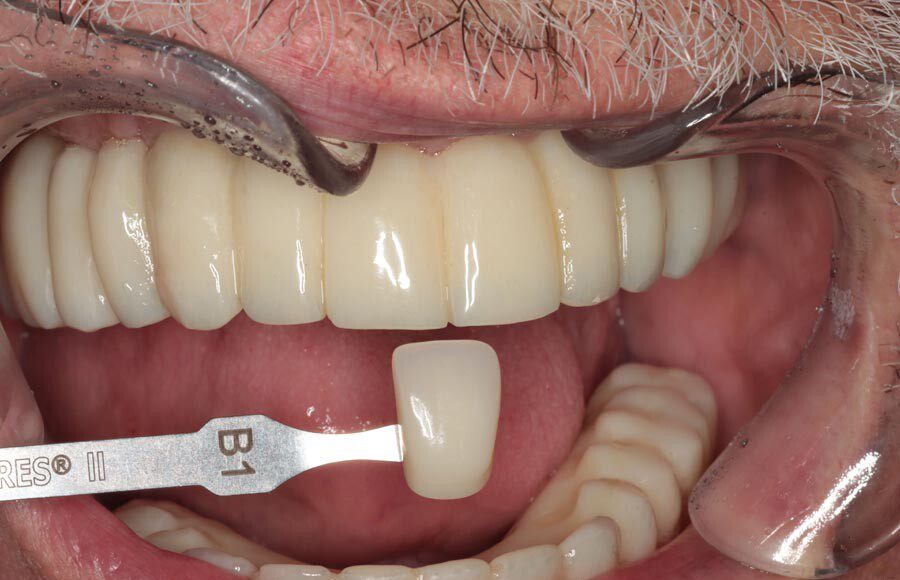

Prototype try-in, smile. The temporary bridges are removed and the prototypes placed. This is where the most scrutiny takes place as we want the patient and family to be thrilled with the appearance and bite. This is the last time changes can be made.